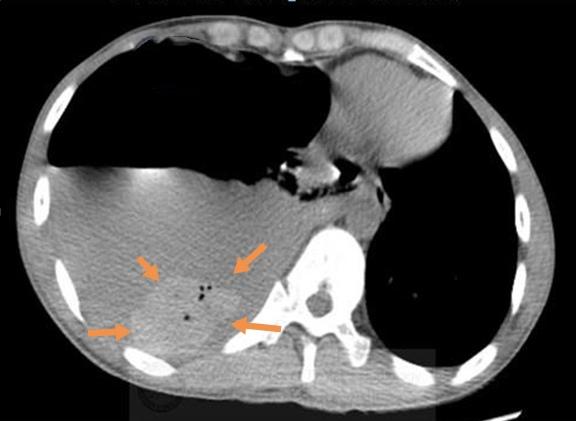

再看纵隔窗:

在大量灰色的胸水里,有一块椭圆形的小团块沉在水底,里面还有4个小气泡。

这是什么东西?

影像科值班医生是个吃货,开玩笑道:“血块吧?猪肉摊上带着小气泡的猪血就是这个样子。”

还真是,相似度95%以上,急诊科医生咯噔一下:要当心了!

这个病人不是单纯的液气胸,准确点说,他是自发性血气胸,出血量在400ml以上了。

像上图这个小伙子就相对幸运一点,肺尖部胸膜下的肺大泡(橙色箭头)破裂,引起自发性气胸,没有伴发出血,经导管引流后顺利出院了。